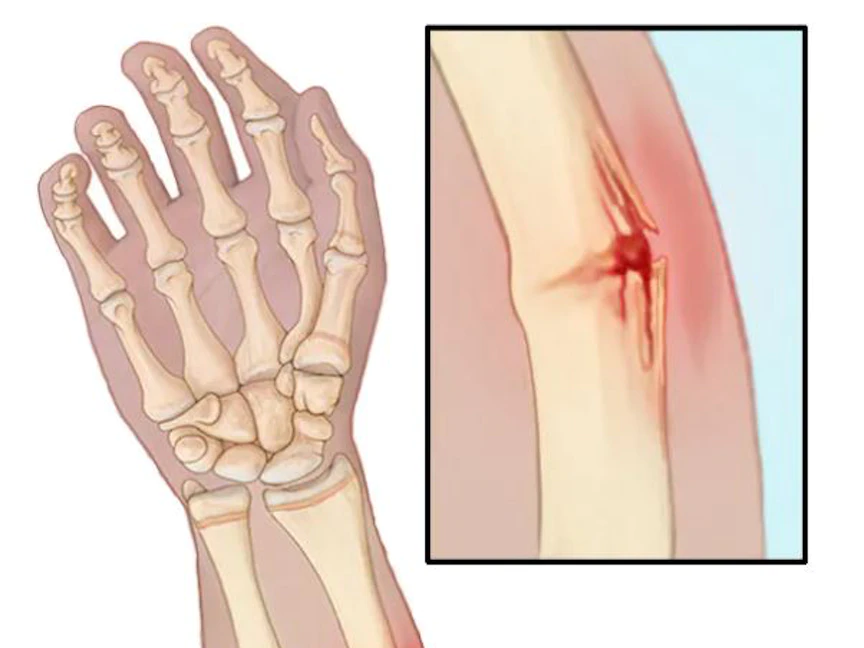

تظهر النتوءات العظمية على امتداد حواف العظام، إذ غالباً ما تَتكون في أماكن التقاء العظام أي في المفاصل ومن الممكن كذلك أن تَتكون على عظام العمود الفقري.

ويَتمثل السبب الأساسي للإصابة بالنتوءات العظمية في تلف المفصل المرتبط بالفصال العظمي، حيث أن معظم النتوءات العظمية لا ينتج عنها ظهور أي أعراض، ومن الممكن أن تَظل لأعوام دون أن يكتشفها الشخص.

يعد تلف المفصل بسبب هشاشة العظام، السبب الأكثر شيوعاً للنتوءات العظمية، فبينما يُحلل الفصام العظمي الغضروف المبطن لأطراف العظام، يحاول الجسم إصلاح هذا الفقدان من خلال تكوين نتواءات عظمية بالقرب من المنطقة المتضررة.